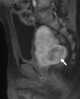

Prostatic rhabdomyosarcoma

Rhabdomyosarcoma (RMS), is a highly aggressive form of cancer that develops from mesenchymal cells that have failed to fully differentiate into myocytes of skeletal muscle. Cells of the tumor are identified as rhabdomyoblasts.There are four subtypes – embryonal rhabdomyosarcoma, alveolar rhabdomyosarcoma, pleomorphic rhabdomyosarcoma, and spindle cell/sclerosing rhabdomyosarcoma. [Source: Wikipedia ]